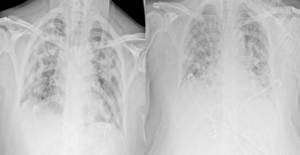

Yeni tip koronavirüse (Kovid-19) yakalanan hastaların 3 ay sonra yapılan yeni bir tarama yöntemiyle incelenen akciğerlerinde hasar oluştuğu tespit edildi. Araştırmada, virüse yakalandıktan 3 ay sonra 'nefes darlığı' ve 'yorgunluk' şikayetinde bulunan 10 hastadan 8'inin akciğerlerinde hasar oluştuğu görüldü.

BBC'de yer alan habere göre, Oxford Üniversitesinden bilim insanları, yaşları 19 ila 69 arasında değişen 10 hastanın akciğerlerini ksenon gazı kullanarak manyetik rezonans (MR) ile taradı.

Tarama esnasında ksenon gazını içine çeken hastalardan 8'i nefes darlığı çektiğini söylerken, akciğer hasarının işaretleri görüldü.

Uzmanlar, hastalarda görülen akciğer hasarının, geleneksel tarama yöntemleri ile tespit edilemediğini belirtti.